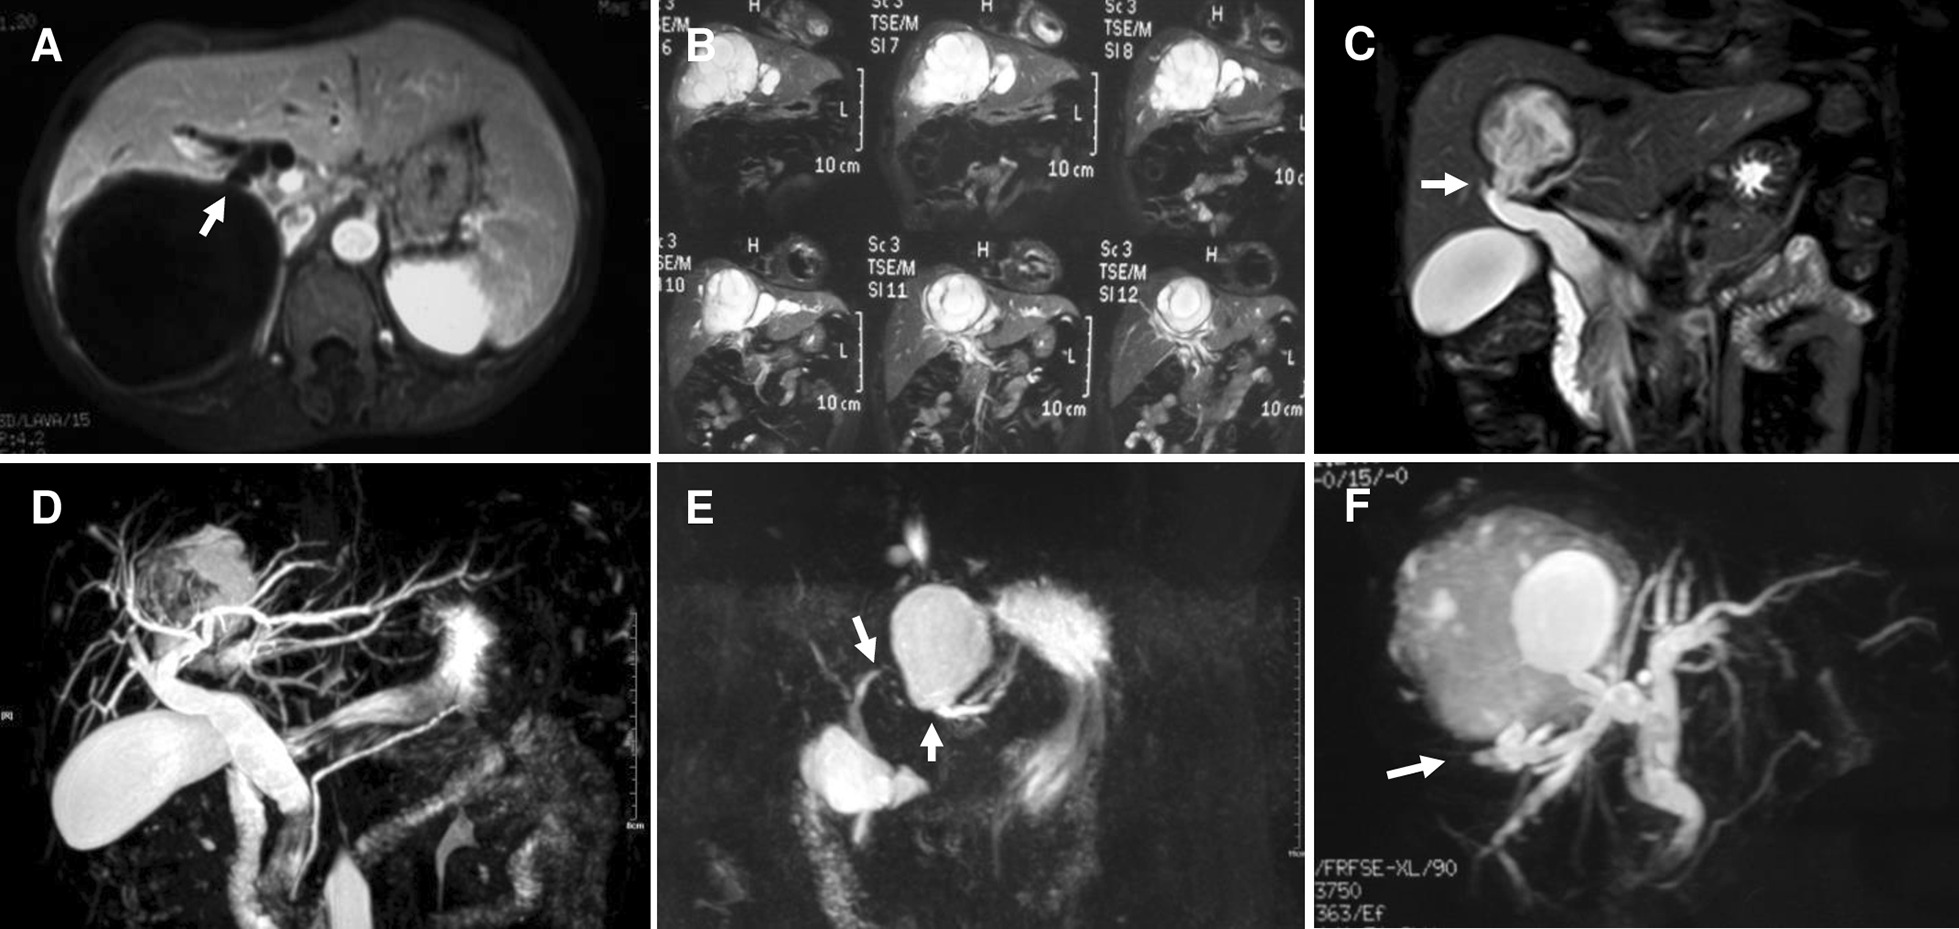

From 2007 March to 2012 December, altogether 660 hepatic CE patients have been hospitalized in our center, and 51 of which (3.5%) without hepatobiliary surgical history underwent PPC in our center due to CE with FCBC. Their most common complaints were abdominal pain, jaundice, nausea and fever. Patient demographics, cyst features and clinical symptoms were presented in Table 1. Preoperative computed tomography (CT) and magnetic resonance imaging and cholangiopancreatography (MR/MRCP) results indicated that, the certain bile duct where the rupture occurred, mostly were perihilar lobular bile ducts (Figs. 1 and 2). PPC was performed in all patients; debris in biliary tracts was removed through CBD using choledochoscopy after cholecystectomy; biliary tract was explored by injecting methylene blue (1:250 dilution with normal saline) to discover the FCBC site (Fig. 3). Owing to the basis of FCBC, setting decompression T-tube and sustaining T-tube drainage have been introduced. Consequently, we retrospectively divided these special subjects into two groups based on their operative procedures (double T-tube drainage group and single T-tube drainage group, specifically mentioned blow), forming this research cohort.